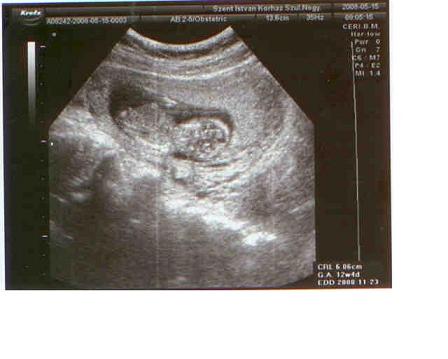

Most hétvégén lehet elmegyünk 4D-re. 16 hetes leszek már szombaton, és ilyenkor már tökjól látszik a baby, meg a nemét is nagyon-nagyon szeretném tudni, úh beszélgetek vele folyamatosan, hogy igérje meg, h széttárj a lábikóit, és akkor elmegyünk meglesni őt...de ha rossz lesz, és még úgy is forul, h nem láthatjuk rendesen, akkor örök harag egy időre, mert 150fontba kerül. (52e ft)

Kérdés. Én hivatalosan mensi szerint nov.1-re lettem volna kiírva, de a 12 hetes uh-n 3 nappal idősebbnek minősítették a babyt, így okt 29 lett belőle.Szerintetek melyiket vegyem "konkrétnak"? Az az igazság, hogy 3 nappal szerintem nem fogant hamarabb, esetleg 1 vagy 2-vel...úh most nemtom... Segítsetek!